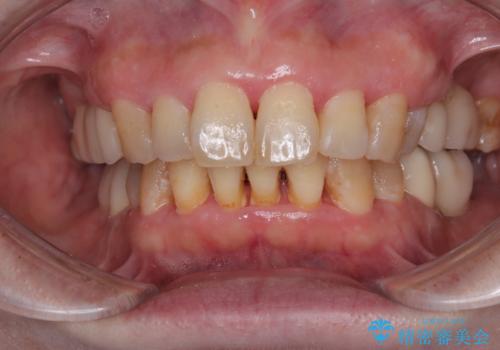

- インプラント治療を前提に下顎の部分矯正を始めたものの、そのまま長い間放置しているとのことで来院された患者様です。

全体的に歯肉が腫れており、歯周病により抜歯をしなければならない歯がある状態でした。

治療前は磨き残しが多く見られ、全体的に歯肉が腫れている状態でしたが、抜歯の必要な歯を抜いたことで口腔内の環境が改善され、磨き残しも少なくなってきました。

インプラントにより咬合が回復したことで、治療開始時に認められた上顎前歯の動揺も改善されました。